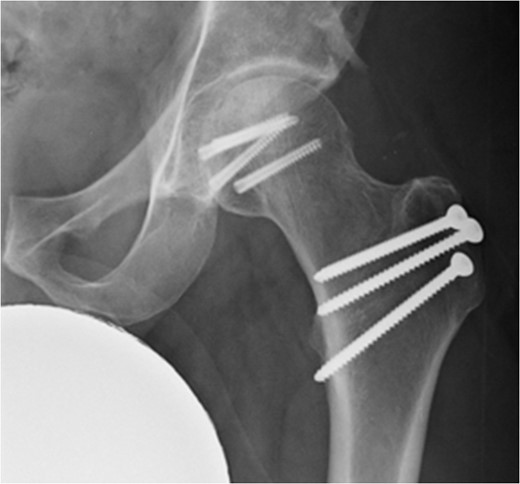

A fit and well man in his 40s had fallen while hiking up a steep hill. He complained of immediate onset, severe left hip pain and inability to move. He was airlifted to our hospital and was found to have shortened externally rotated left leg. Plain X-rays were performed in the emergency department (Fig. 1) identifying isolated fracture–dislocation of the left hip. Computed tomography (CT) was performed while en route to theatre (Figs 2 and 3).

AP radiograph of left hip showing fracture–dislocation of femoral head.